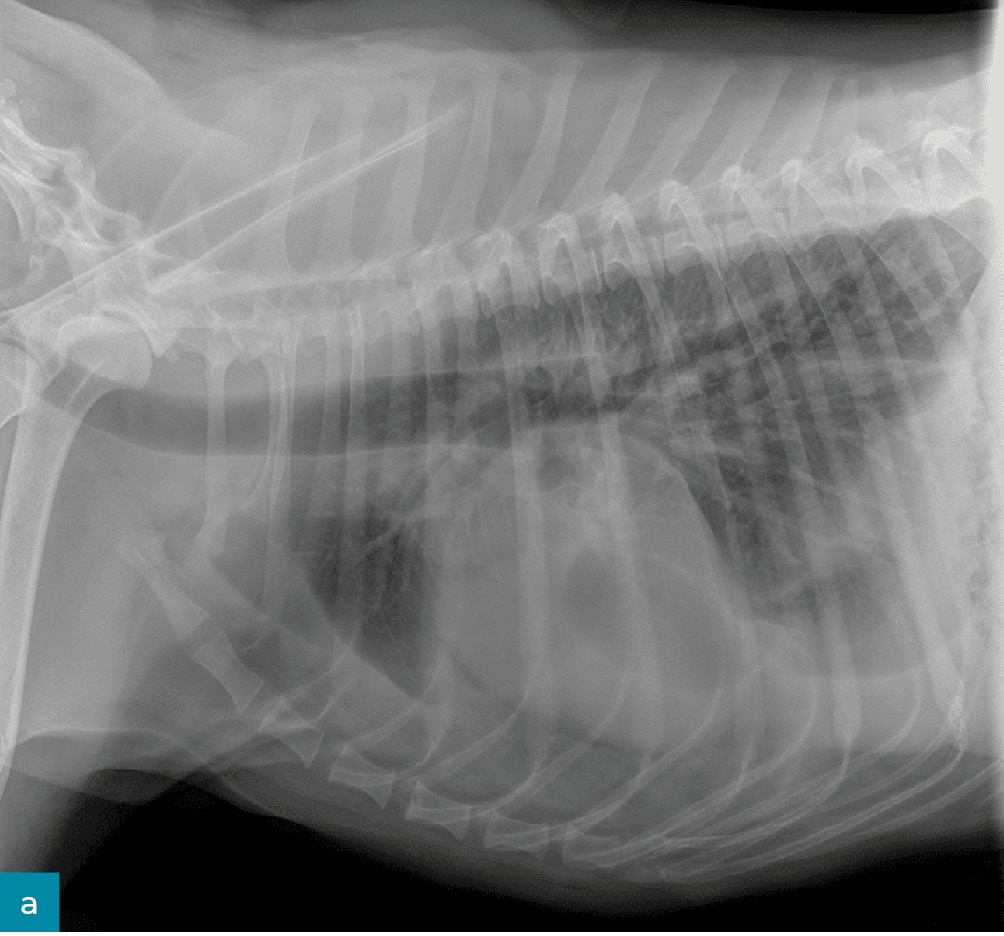

Lekarz weterynarii podstawowej opieki zdrowotnej poinformował, że badanie kliniczne pacjenta było w normie: temperatura wynosiła 38,2°C, częstość pracy serca 90 uderzeń/min, a częstość oddechów 35/min przy normalnym wysiłku. Odnotowano utratę masy ciała o 2 kg – podczas corocznego badania sześć miesięcy wcześniej wynosiła ona 33 kg. Wykonano przesiewowe badanie rentgenowskie jamy brzusznej oraz klatki piersiowej i zidentyfikowano płyn w przestrzeni opłucnowej (ryc. 2). Pacjent został skierowany do placówki specjalistycznej/ratunkowej w celu przeprowadzenia dodatkowej diagnostyki.

• Medium 1268

• Medium 1306

Ryc. 2. Prawe profilowe (a) i brzuszno-grzbietowe (b) zdjęcie klatki piersiowej pacjenta z chłonkopiersiem, pokazujące płyn w przestrzeni opłucnowej.

W ośrodku ratunkowym pacjent był ożywiony, czujny i reagował na bodźce. Stwierdzono szmer skurczowy serca stopnia 2/6. Radiogramy klatki piersiowej potwierdziły płyn w jamie opłucnej i wykazały łagodną niedodmę doogonowych pól płucnych. Podczas nakłucia klatki piersiowej usunięto około 3 ml białego, mlecznego płynu z lewej doczaszkowej części klatki piersiowej i około 20 ml z prawej części klatki piersiowej. Rodzaje płynu gromadzącego się w przestrzeni opłucnej obejmują przesięk, zmodyfikowany przesięk, wysięk oraz wysięk limfatyczny. Biorąc pod uwagę wygląd płynu, podejrzewano wysięk limfatyczny. Ostateczne rozpoznanie chłonkopiersia opiera się na wykryciu w płynie stężenia triglicerydów wyższego niż w surowicy. Płyn został przesłany wraz z krwią i moczem do badań diagnostycznych.